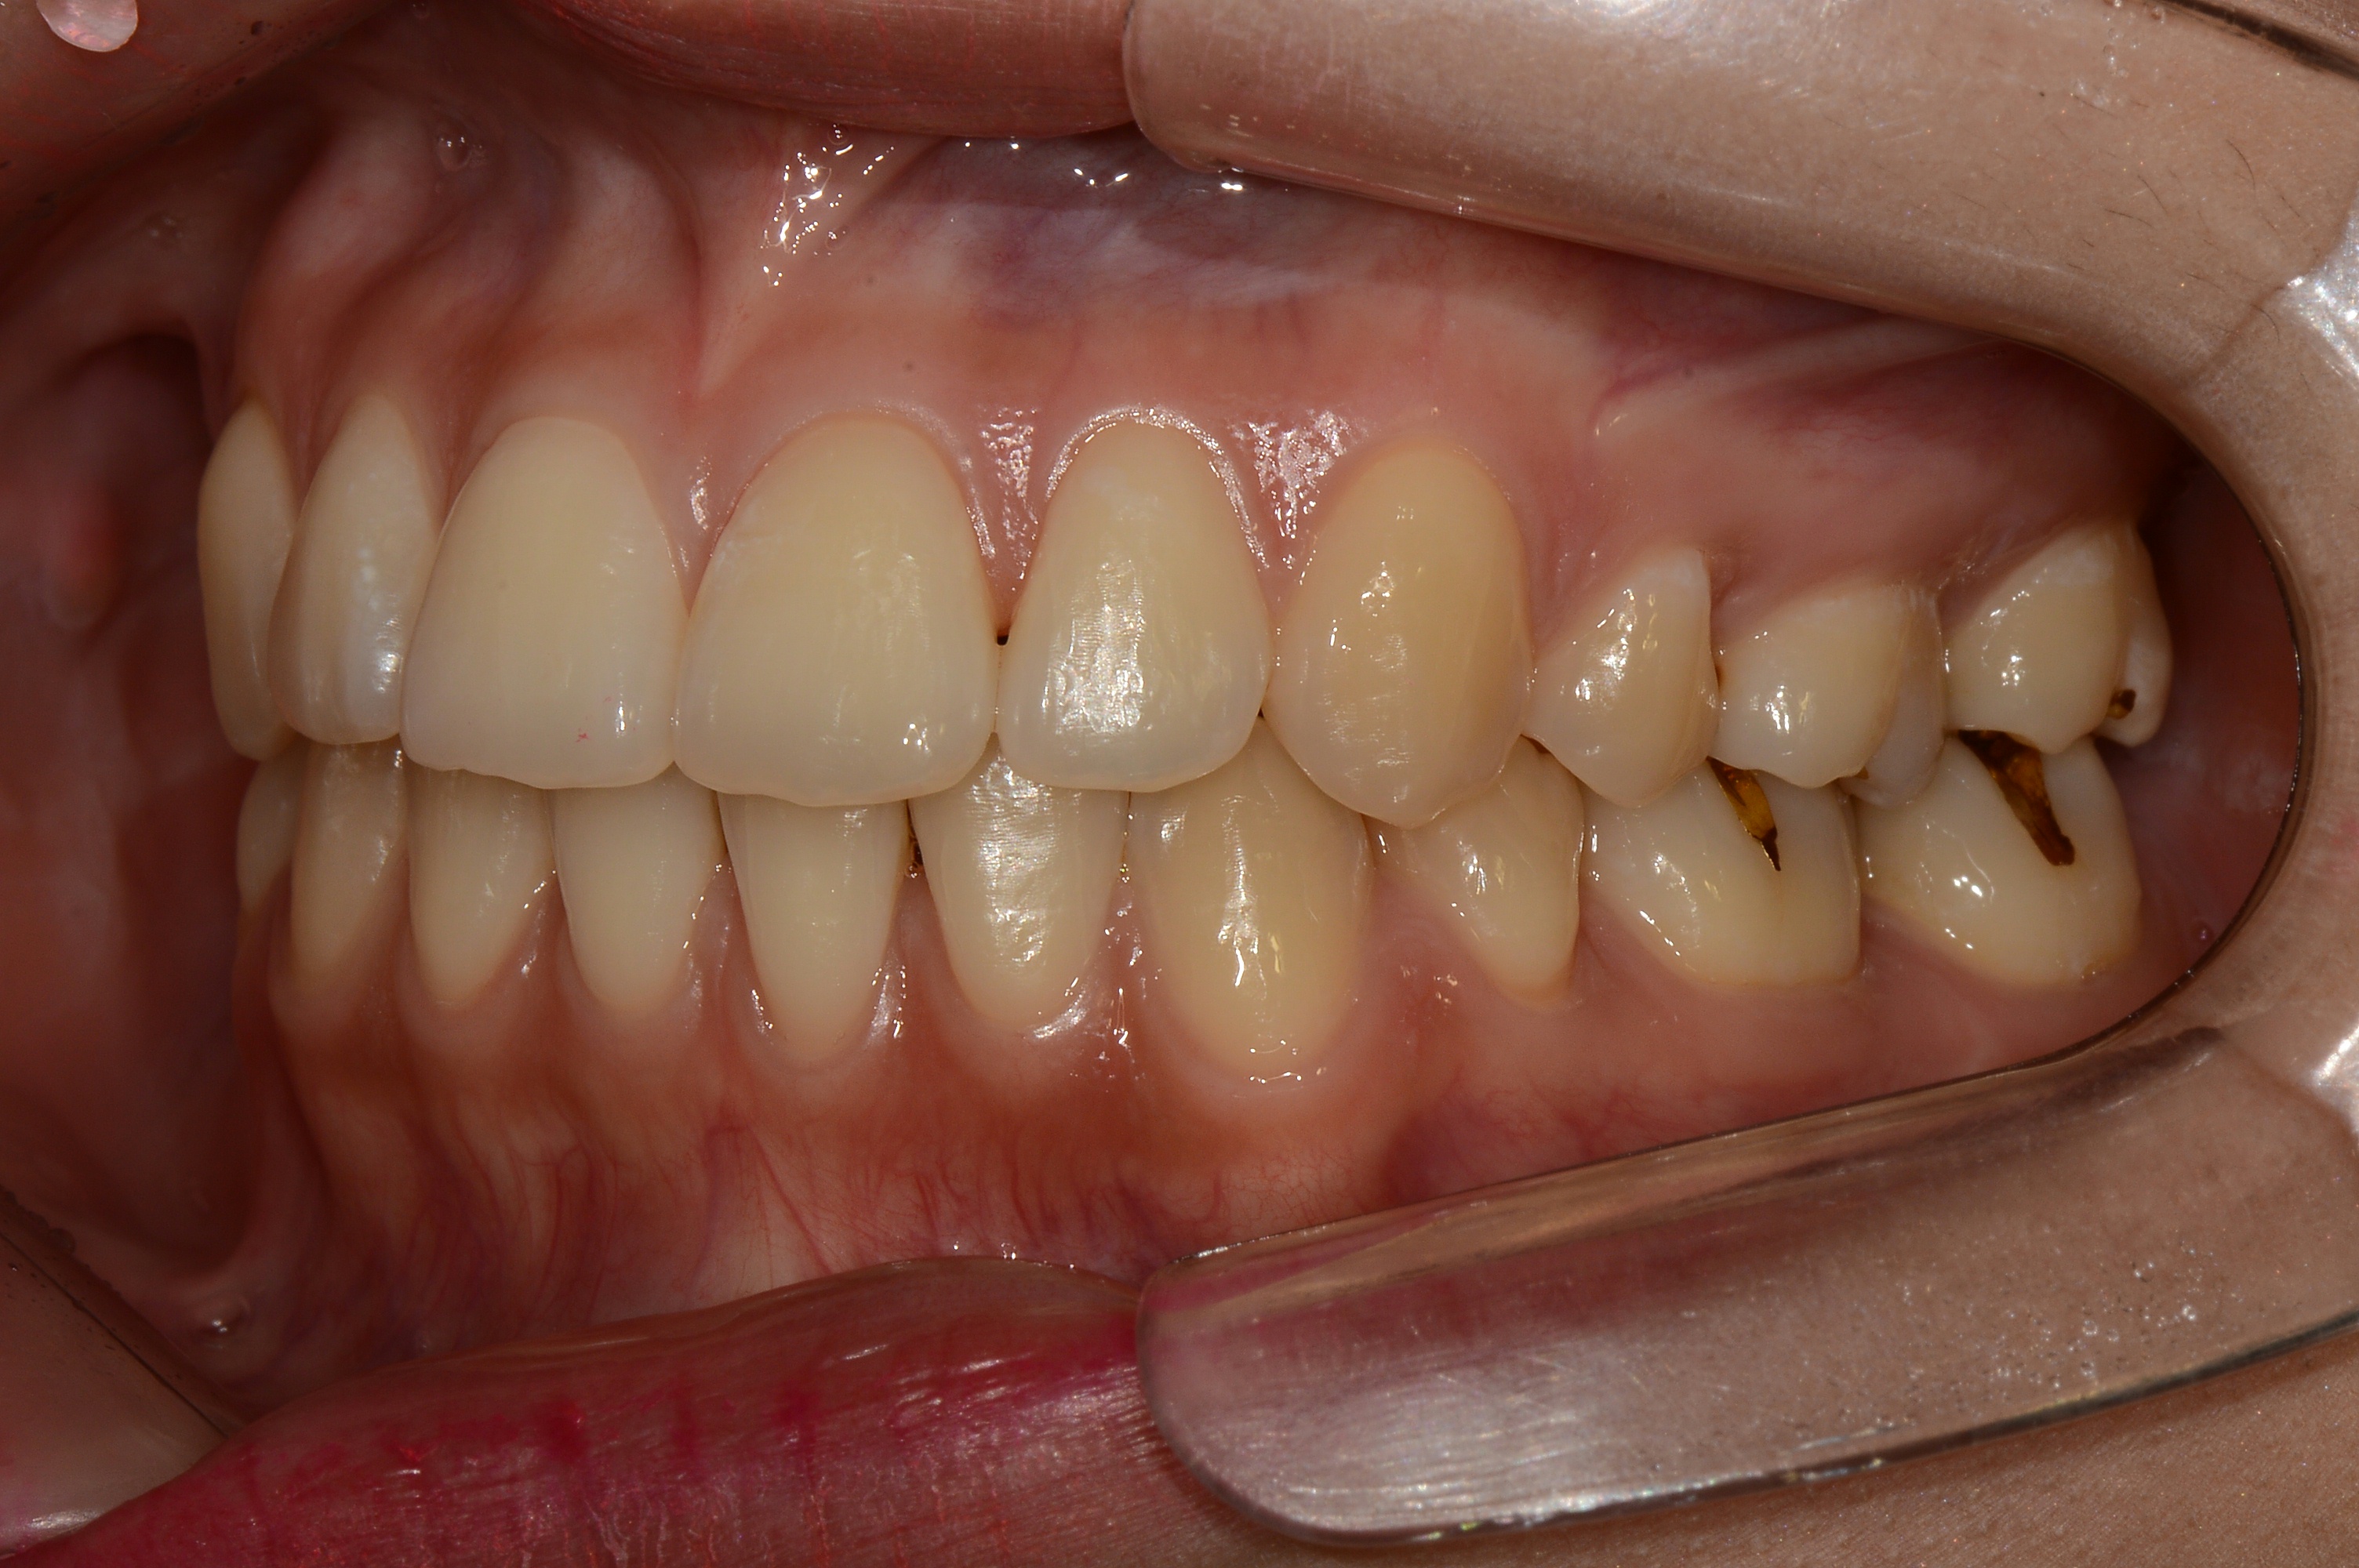

치료 전 사진입니다.